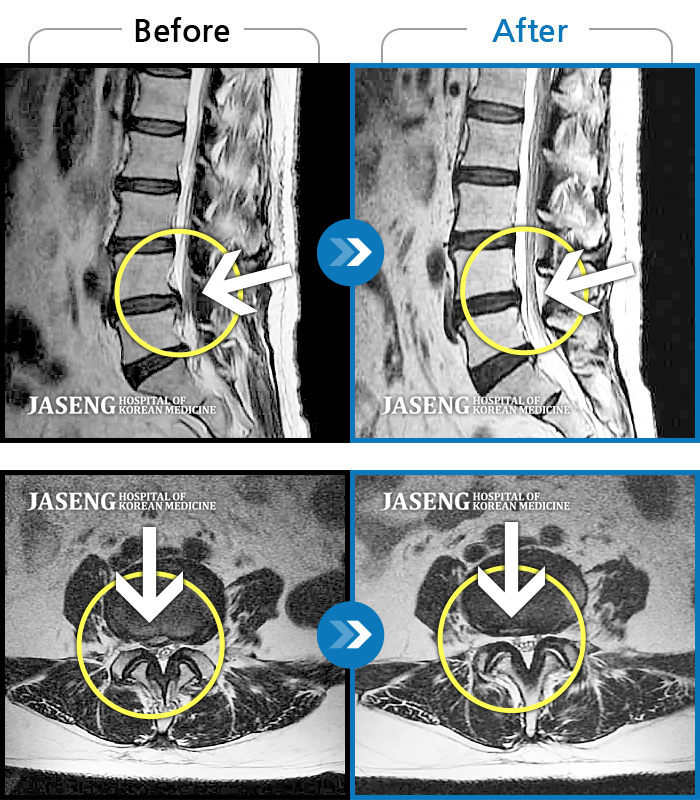

Xray 와 MRI 검사를 받았고

4번5번 척추사이 협착증과 유종이 원인이라고 하면서

한방 비수술치료로 2달동안 치료하면 나을 수가 있다고 말씀하셨고, 만약 한방치료로도 낫지 않으면 큰 대학병원 수술을 받아야 한다고 하면서 한방 비수술 치료를 권장해 주셔서, 박정우원장님의 치료를 받기 시작하였다.

12월20일까지 두 달 정도 치료를 마친 결과,

거의 정상상태로 회복 되었으며, 현재는 집에서 꾸준하게 체조와 가벼운 운동으로 관리하고 있습니다.